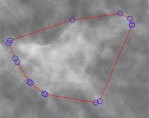

C. 关键点生成

多个像素构成检测到的病灶的轮廓。然而,人们在修改轮廓时难以调整大量点,这是一项耗时任务。第二节中的分析表明,人工标注结果类似于凸包。因此,所提方案生成凸包而非完整轮廓,分别如图1(c)和图2(c)所示。此外,当初始关键点数量超过20个时,我们剔除部分关键点。关键点保留判定定义如下,

在(3)中,第i个关键点pi被保留为Θ(pi)=1。符号||pi−pi-1||表示pi与pi-1之间的欧氏距离。阈值τdist控制保留的关键点数量。图1(d)和图2(d)分别展示了检测到的肿块和检测到的钙化灶对应的最终关键点构成的多边形。